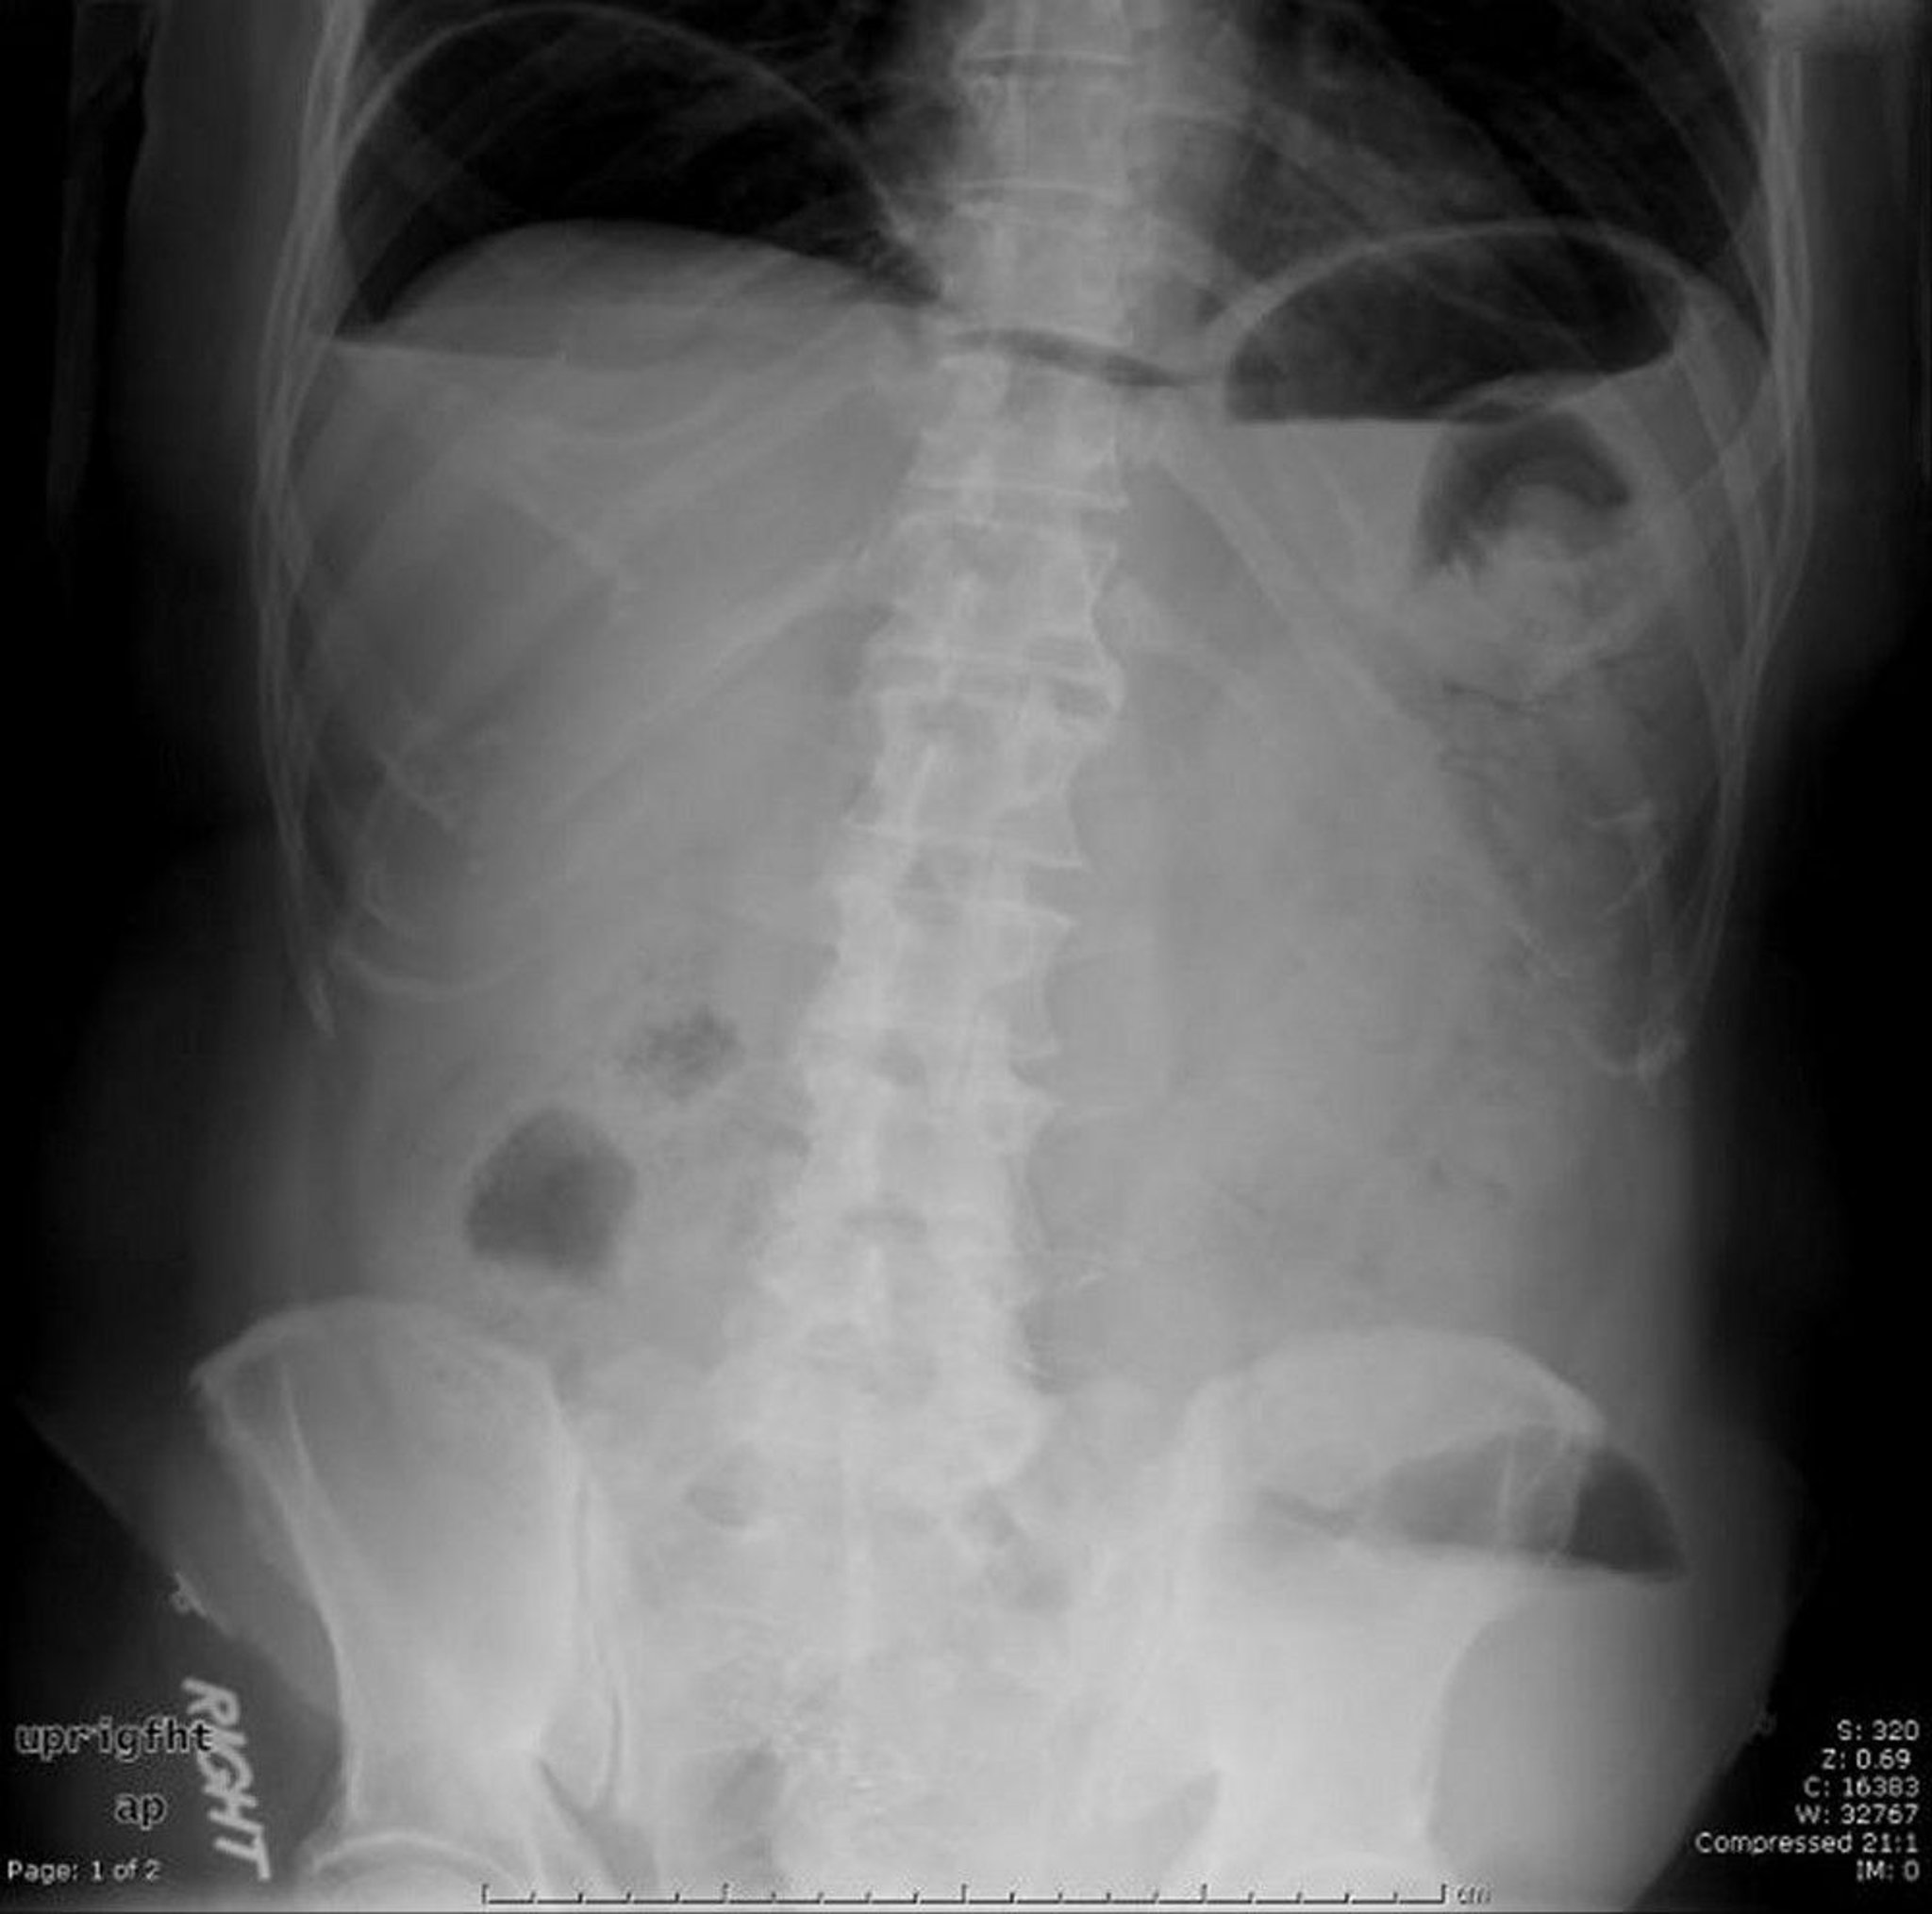

This abdominal radiograph shows free air caused by a perforation.

Image provided by Parswa Ansari, MD.